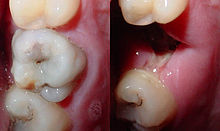

Most importantly, whether the carious lesion is cavitated or non-cavitated dictates the management. Clinical assessment of whether the lesion is active or arrested is also important. Noncavitated lesions can be arrested and remineralization can occur under the right conditions. However, this may require extensive changes to the diet (reduction in frequency of refined sugars), improved oral hygiene (toothbrushing twice per day with fluoride toothpaste and daily flossing), and regular application of topical fluoride. More recently, Immunoglobulin Y specific to Streptococcus mutans has been used to suppress growth of S mutans.[133] Such management of a carious lesion is termed "non-operative" since no drilling is carried out on the tooth. Non-operative treatment requires excellent understanding and motivation from the individual, otherwise the decay will continue.

Once a lesion has cavitated, especially if dentin is involved, remineralization is much more difficult and a dental restoration is usually indicated ("operative treatment"). Before a restoration can be placed, all of the decay must be removed otherwise it will continue to progress underneath the filling. Sometimes a small amount of decay can be left if it is entombed and there is a seal which isolates the bacteria from their substrate. This can be likened to placing a glass container over a candle, which burns itself out once the oxygen is used up. Techniques such as stepwise caries removal are designed to avoid exposure of the dental pulp and overall reduction of the amount of tooth substance which requires removal before the final filling is placed. Often enamel which overlies decayed dentin must also be removed as it is unsupported and susceptible to fracture. The modern decision-making process with regards the activity of the lesion, and whether it is cavitated, is summarized in the table.[134]

Destroyed tooth structure does not fully regenerate, although remineralization of very small carious lesions may occur if dental hygiene is kept at optimal level.[15] For the small lesions, topical fluoride is sometimes used to encourage remineralization. For larger lesions, the progression of dental caries can be stopped by treatment. The goal of treatment is to preserve tooth structures and prevent further destruction of the tooth. Aggressive treatment, by filling, of incipient carious lesions, places where there is superficial damage to the enamel, is controversial as they may heal themselves, while once a filling is performed it will eventually have to be redone and the site serves as a vulnerable site for further decay.[13]

In general, early treatment is quicker and less expensive than treatment of extensive decay. Local anesthetics, nitrous oxide ("laughing gas"), or other prescription medications may be required in some cases to relieve pain during or following treatment or to relieve anxiety during treatment.[135] A dental handpiece ("drill") is used to remove large portions of decayed material from a tooth. A spoon, a dental instrument used to carefully remove decay, is sometimes employed when the decay in dentin reaches near the pulp.[136] Some dentists remove dental caries using a laser rather than the traditional dental drill. A Cochrane review of this technique looked at Er:YAG (erbium-doped yttrium aluminium garnet), Er,Cr:YSGG (erbium, chromium: yttrium-scandium-gallium-garnet) and Nd:YAG (neodymium-doped yttrium aluminium garnet) lasers and found that although people treated with lasers (compared to a conventional dental "drill") experienced less pain and had a lesser need for dental anaesthesia, that overall there was little difference in caries removal.[137] Once the caries is removed, the missing tooth structure requires a dental restoration of some sort to return the tooth to function and aesthetic condition.